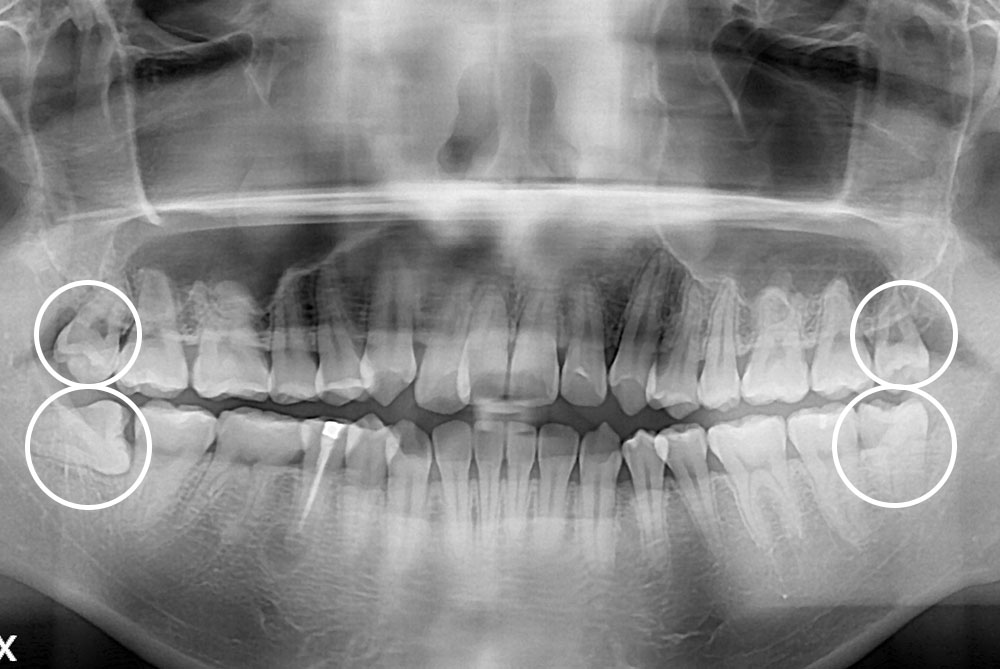

[사랑니] 매복 사랑니 발치

치료후 : 2018-11-09

세종치과는 구강악안면외과학 박사이신 원장님이 발치하는 치과입니다.